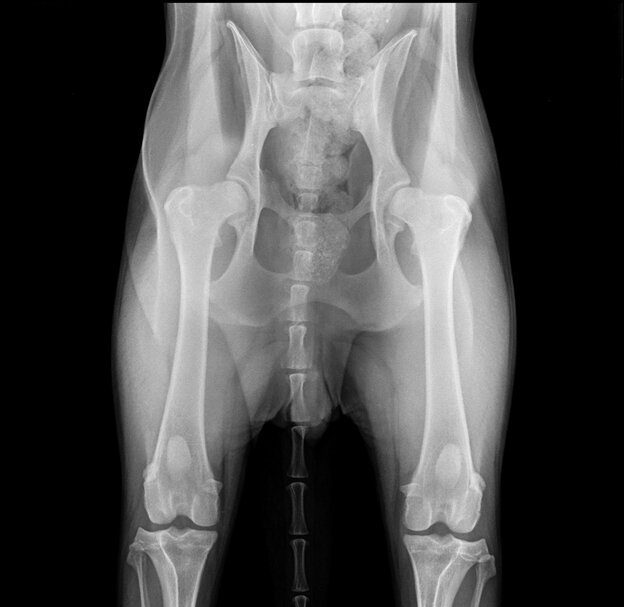

Тяжелая степень дисплазии тазобедренных суставов